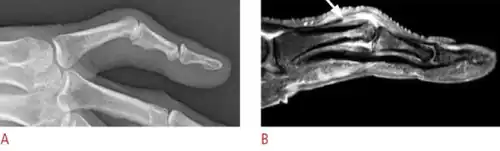

Boutonniere deformity is a deformed position of the fingers or toes, in which the joint nearest the knuckle (the proximal interphalangeal joint, or PIP) is permanently bent toward the palm while the farthest joint (the distal interphalangeal joint, or DIP) is bent back away (PIP flexion with DIP hyperextension). Causes include injury,[1] inflammatory conditions like rheumatoid arthritis, and genetic conditions like Ehlers-Danlos syndrome.[2]

This flexion deformity of the proximal interphalangeal joint is due to interruption of the central slip of the extensor tendon such that the lateral slips separate and the head of the proximal phalanx pops through the gap like a finger through a button hole (thus the name, from French boutonnière "button hole"). The distal joint is subsequently drawn into hyperextension because the two peripheral slips of the extensor tendon are stretched by the head of the proximal phalanx (note that the two peripheral slips are inserted into the distal phalanx, while the proximal slip is inserted into the middle phalanx). This deformity makes it difficult or impossible to extend the proximal interphalangeal joint.